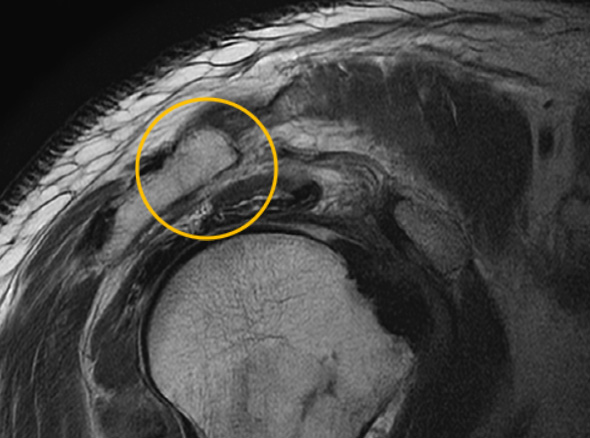

관절 내시경을 통한

견봉 성형술

관절 내시경을 통하여

힘줄 손상을 유발하는 견봉하 골극을 제거합니다.